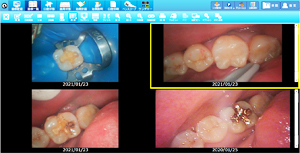

• ラバーダムを使用した治療画像